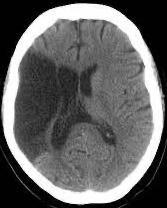

- Tomografia Computadorizada (TC)

De rápida execução, permite a diferenciação entre A.V.C. isquêmico e hemorrágico, monitoramento da evolução do A.V.C. e detecção de condições concomitantes.

AVC ISQUÊMICO

(ÁREA ESCURA)

AVC HEMORRÁGICO

(ÁREA BRANCA)